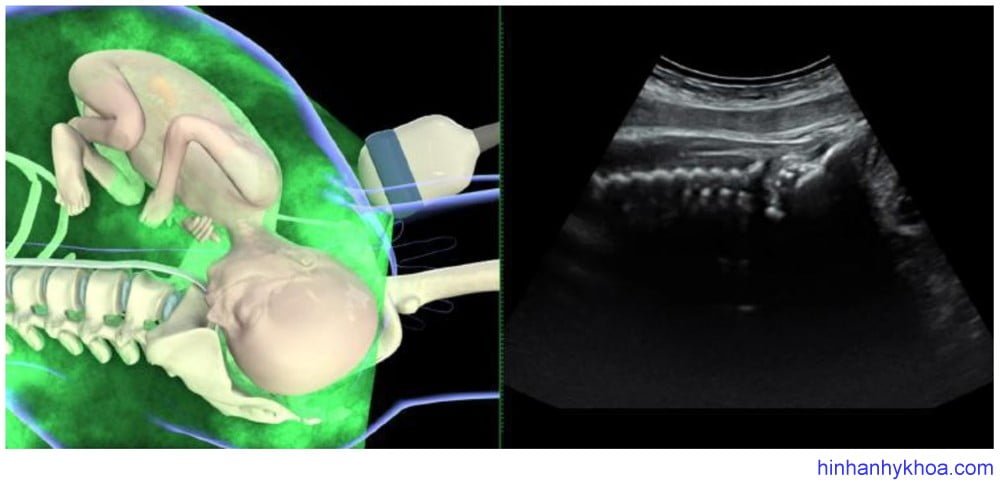

Siêu âm đánh giá kiểu thế thai được thực hiện tốt nhất qua ngã bụng ở mặt cắt ngang và đứng dọc. Đầu dò được đặt nằm ngang trên bụng mẹ, lấy mặt cắt ngang qua phần bụng trên hoặc ngực của thai, từ đó xác định vị trí cột sống. Sau đó di chuyển đầu dò xuống đến vùng trên xương mu của mẹ để thấy được đầu thai. Điểm mốc để xác định vị trí chẩm đó là nếu thấy hai hốc mắt thai có nghĩa là kiểu thế chẩm sau, thấy đường echo dày dọc giữa hai

bán cầu não là kiểu thế ngang, thấy vùng chẩm và cột sống cổ là kiểu thế trước [81] (Hình 1 và 2). Đám rối mạch mạc hai bên thường phân kì hướng về phía chẩm, cũng hữu ích trong việc xác định kiểu thế [47].

Hình 1: hình ảnh siêu âm ngã bụng mặt phẳng đứng dọc cho thấy kiểu thế chẩm trước (Youssef và cs. [81])